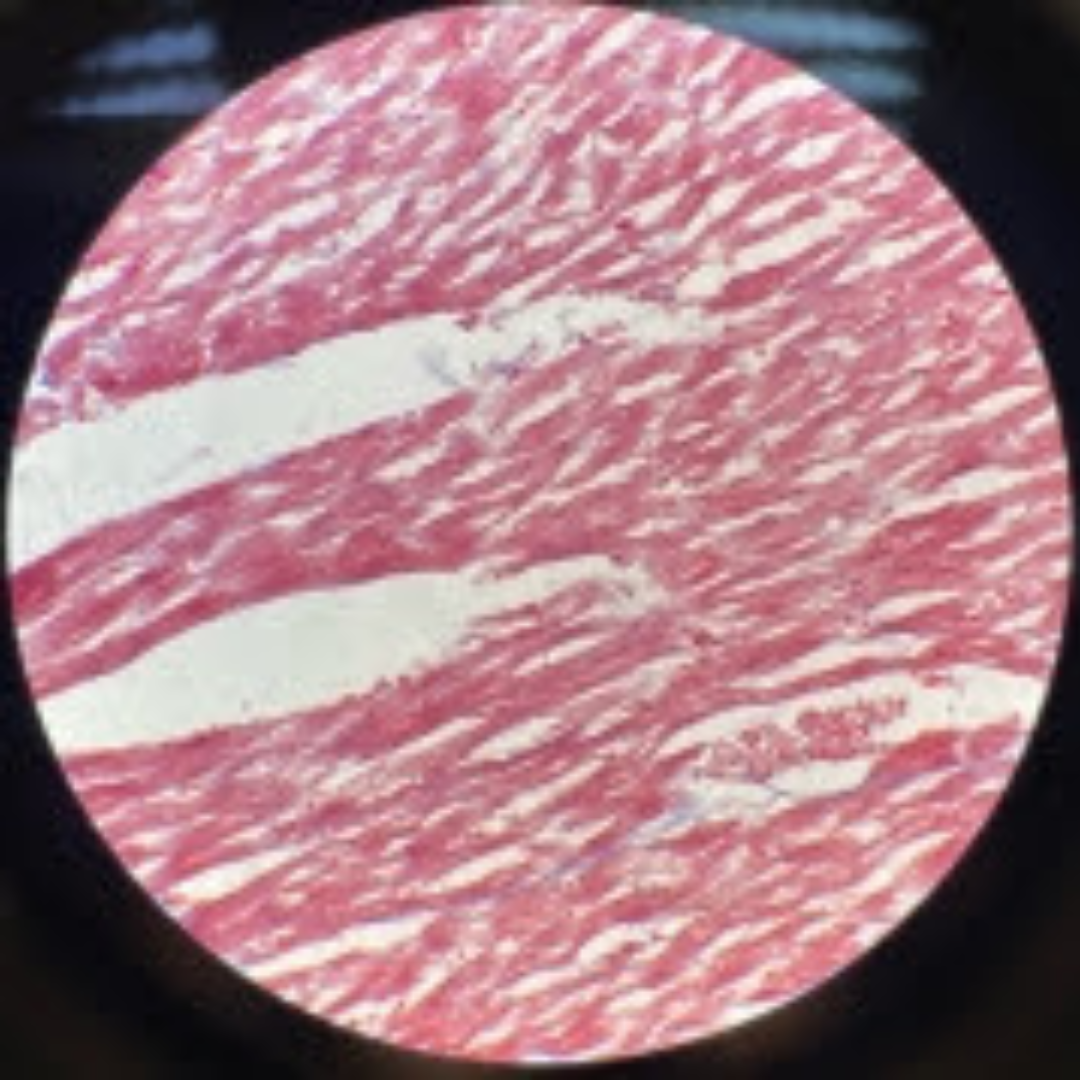

Dense Regular Collagenous Connective Tissue (Fibrous Tissue)